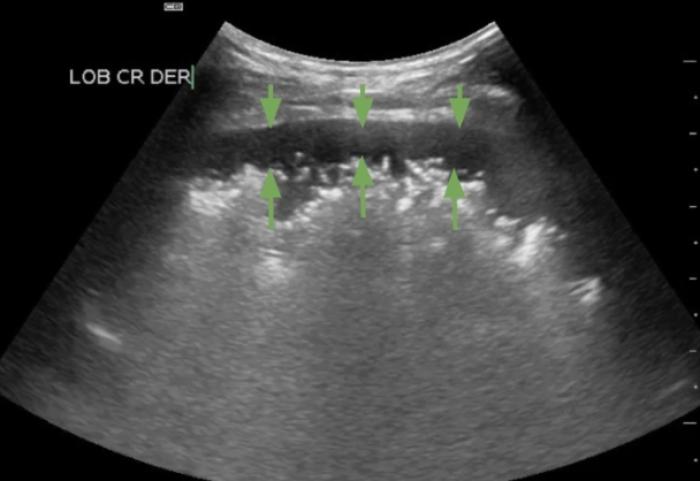

Comenzaremos posicionando el transductor perpendicular a las costillas en uno de los espacios intercostales, pudiendo evaluar al menos el espacio entre dos costillas, la línea PP y no más de 2-3 cm de profundidad de campo (Figura 1A-B).

Son visibles en todo pulmón bien ventilado, pero también estarán presentes en el neumotórax por lo que en este punto es vital observar el deslizamiento de la LP para su diferenciación (Figura 3A-B).